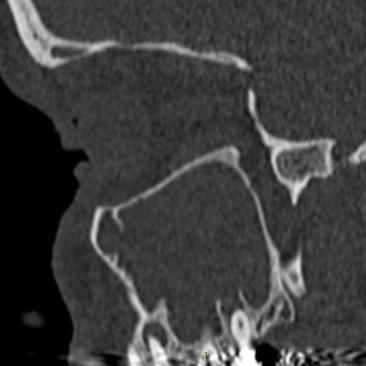

Características de Imagens

De forma geral, a sinusite odontogênica demonstra, em imagens de tomografia computadorizada, obliteração parcial ou total do seio maxilar afetado, além de espessamento da mucosa sinusal, nível líquido (sugestivo de infecção ativa), destruição ou erosão óssea do assoalho sinusal (sinal de origem odontogênica), lesão periapical associada a um dente posterior (principal achado diagnóstico), comunicação oroantral em casos de perfuração do seio, e até mesmo corpos estranhos, em casos de procedimentos odontológicos.